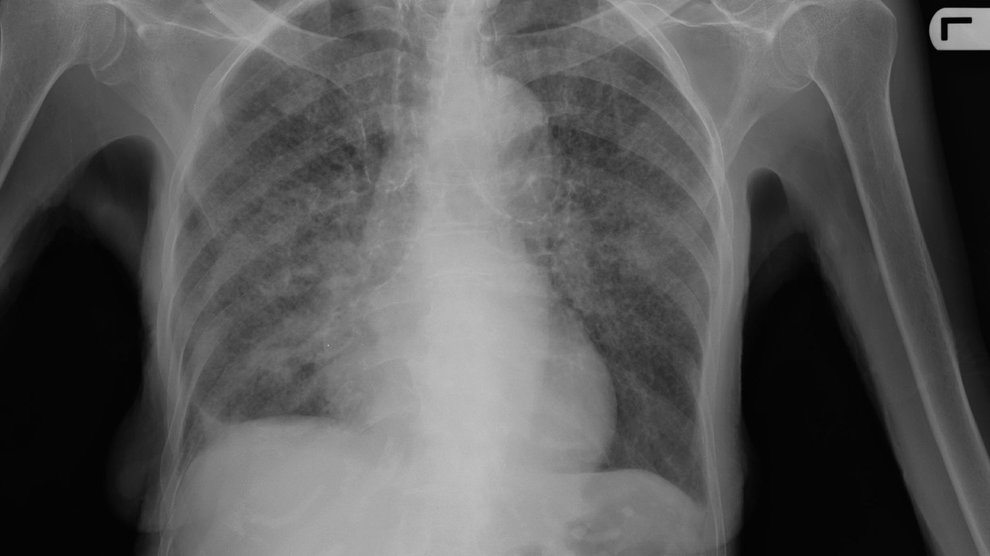

Creative collaborations are uncovering a wealth of new drugs that could help tame drug resistant tuberculosis. NOVA Next contributor Amanda B. Keener